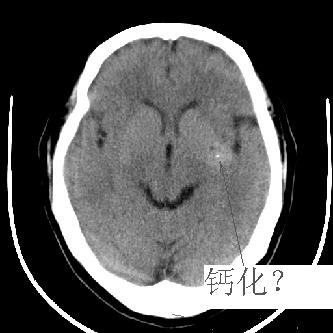

标题: CT4588:是出血吗?

44 f,平时头晕,有高血压病史,近日加重。其它检查无异常。

尽管密度类似于出血,但其密度明显不均匀,中间有多枚小点状致密影似钙化。同时,病灶周围没有水肿,没有占位效应,临床又没有其他症状。

有沙砾样钙化,考虑血管瘤。建议增强。

灶内钙化.逮议ct增强.

左侧豆状核后部不均匀高密度影,中间有斑点状钙化灶,周围无水肿及占位效应,考虑血管瘤。

病人做了mr,诊断为:海绵状血管瘤.